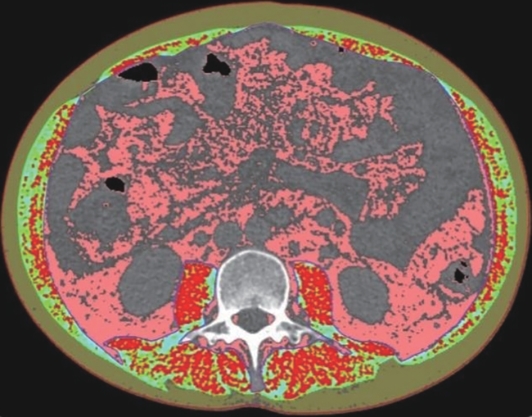

Value of internal stratification analysis of abdominal wall muscles in predicting complications after orthotopic liver transplantation

Xin SHI, Chongxiao LIANG, Bei ZHANG, Jiping WANG

2025, 41(2): 314-321. DOI: 10.12449/JCH250218

Abstract(759) HTML (355) PDF (3265KB)(57)

Abstract:

Objective  To divide the muscle into different subzones according to different density ranges using the stratified analysis on the basis of myosteatosis, and to investigate the effect of muscle density changes on complications (Clavien-Dindo grade ≥Ⅲ) after orthotopic liver transplantation (OLT).  Methods  A retrospective analysis was performed for the medical records of 145 patients who underwent OLT in The First Hospital of Jilin University from May 2013 to September 2020, and with the plain CT scan images of the largest level of lumbar 3 vertebrae of each patient as the original data, Neusoft Fatanalysis software was used to measure related muscle parameters. The independent-samples t test was used for comparison of normally distributed continuous data between two groups, and the Mann-Whitney U test was used for comparison of non-normally distributed continuous data between two groups. The chi-square test or Fisher test was for comparison of categorical data between two groups. RIAS software was used to extract clinical features and perform analysis and modeling, and three machine learning models of logistic regression (LR), support vector machine (SVM), and random forest (RFC) were constructed. The receiver operating characteristic (ROC) curve, the calibration curve, and the decision curve were plotted for each model to calculate the area under the ROC curve (AUC), sensitivity, specificity, precision, F1 score, and accuracy.  Results  The three machine learning models of LR-C, SVM-C, and RFC-C were established based on the 7 clinical features before muscle stratification analysis, among which the RFC-C model had an AUC of 0.803, a sensitivity of 0.588, and a specificity of 0.778 in the test set. Among the models of LR-CS, SVM-CS, and RFC-CS established based on the 16 clinical features after muscle stratification analysis, the LR-CS and SVM-CS models had an AUC of 0.852 in the test set, with a sensitivity of 0.765 and 0.706, respectively, and a specificity of 0.889 and 0.926, respectively. Comparison of the AUC, sensitivity, specificity, precision, F1 score, and accuracy of each model in the test set before and after muscle stratification analysis showed that there were improvements in the parameters of the predictive model after muscle stratification analysis. Comparison of the decision curves and calibration curves of each predictive model showed that the LR-CS and SVM-CS models had good efficacy in predicting postoperative complications (Clavien-Dindo grade≥Ⅲ) in OLT patients.  Conclusion  On the basis of myosteatosis, the division of the muscle into different subzones according to different densities using the stratified analysis has a certain value in predicting postoperative complications in patients with OLT.